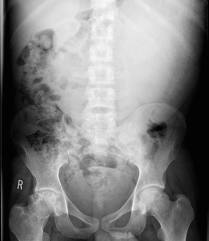

This pt. has sickle cell disease with splenomegaly.

What is the DDx from Splenomegaly?